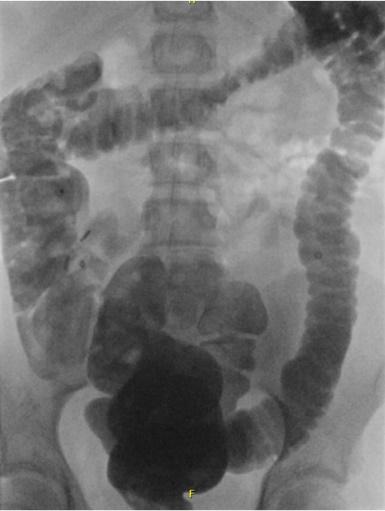

Coloninloop: Dit is een onderzoek waarbij contrastvloeistof via het poepgat wordt ingebracht om de dikke darm beter te bekijken. Daarna worden er een aantal röntgenfoto's na elkaar gemaakt, zodat de darm goed te zien is. Zo kan de arts goed beoordelen of de darm lang, wijd of kronkelig is.- Als uw kind dit spannend vindt, kan een medisch pedagogisch zorgverlener u en uw kind helpen om ervoor te zorgen dat dit proces zo soepel mogelijk verloopt.

- Coloninloop: Onderzoek waarin de dikke darm zichtbaar wordt gemaakt met vloeistof en rontgenfoto’s.